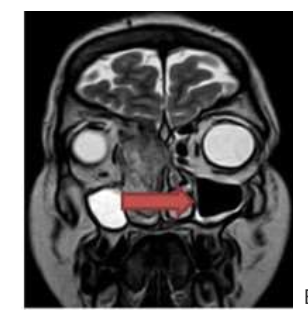

En la siguiente imagen, se observa:]

A. Seno esfenoidal

B. Seno maxilar

c. Seno Etmoidal

d. Seno Frontal